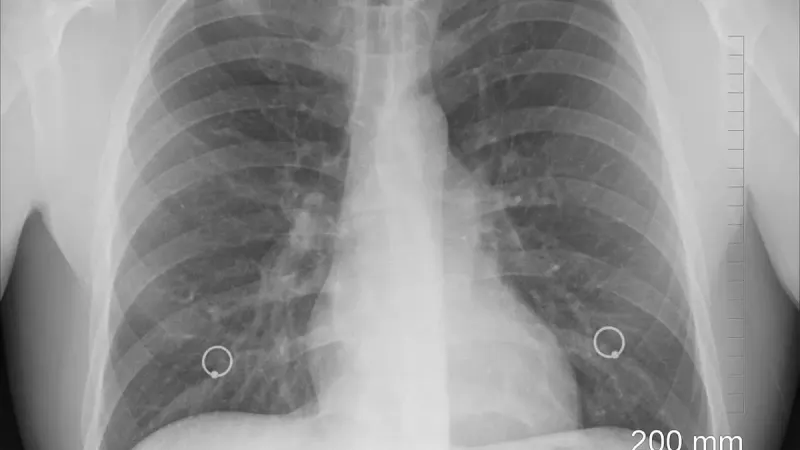

легкие человека Фото: pixabay